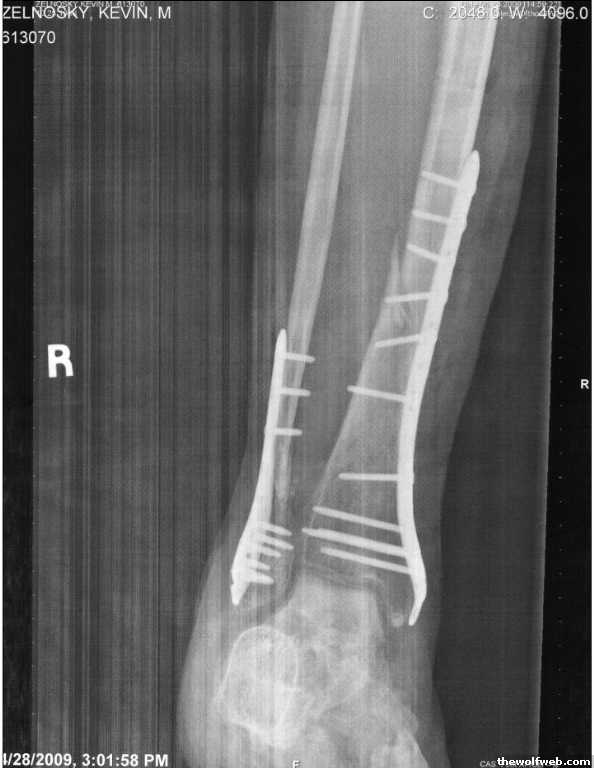

Photo Gallery » Zel » Fixed?

Fixed?